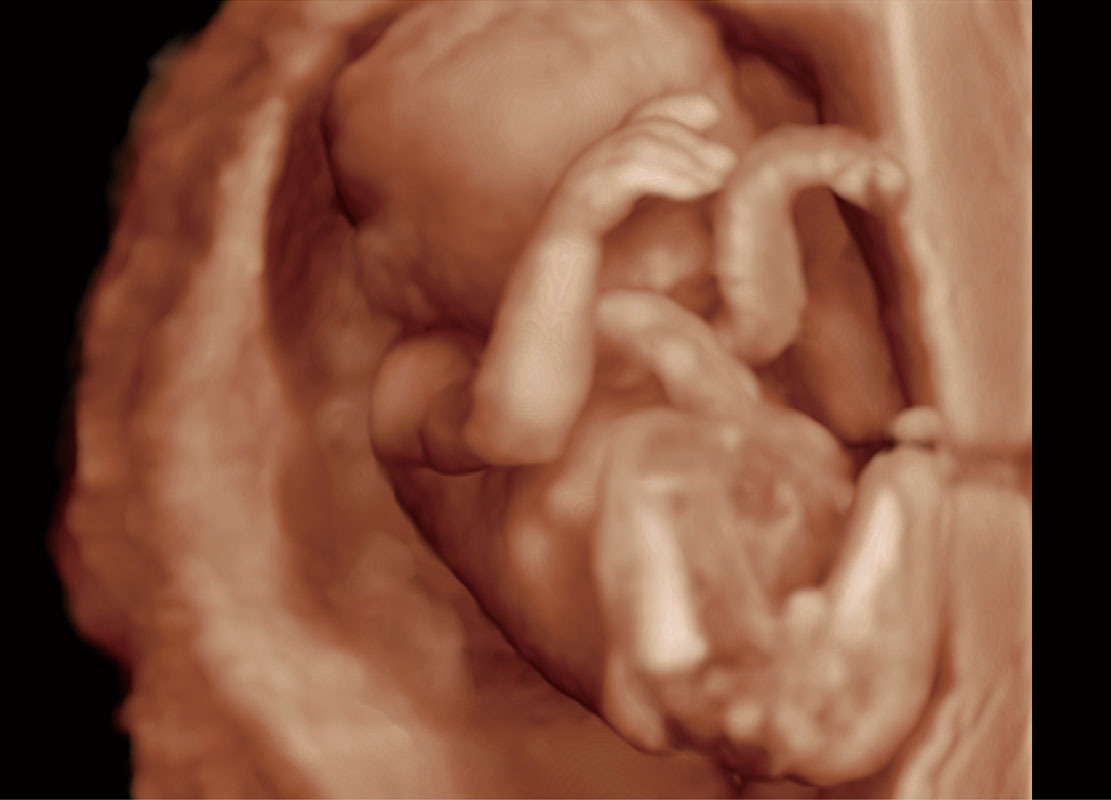

P60在胎儿早孕期超声筛查中为您带来优异的图像质量。

高分辨率容积成像-早孕胎儿

胎儿体循环

光影成像-孕囊